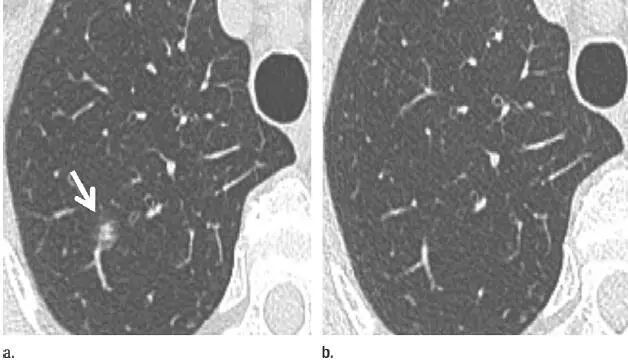

14. 多灶性原发性腺癌

图 14(a)上叶层厚 1 mm 的 CT 横断面图像,显示双侧多个大小不等的半实性结节,且左肺上叶至少包含一个高度可疑(较大、磨玻璃样外观和实性形态)的部分实性结节(箭头)。建议在 3~6 个月后进行首次随访。

(b)与 a 图同次检查时取得的更下部分图像,显示了另一个高度可疑的分叶状 10 mm 大小磨玻璃样结节(箭头),也需要随访。这些图像符合多灶性原发性腺癌表现。